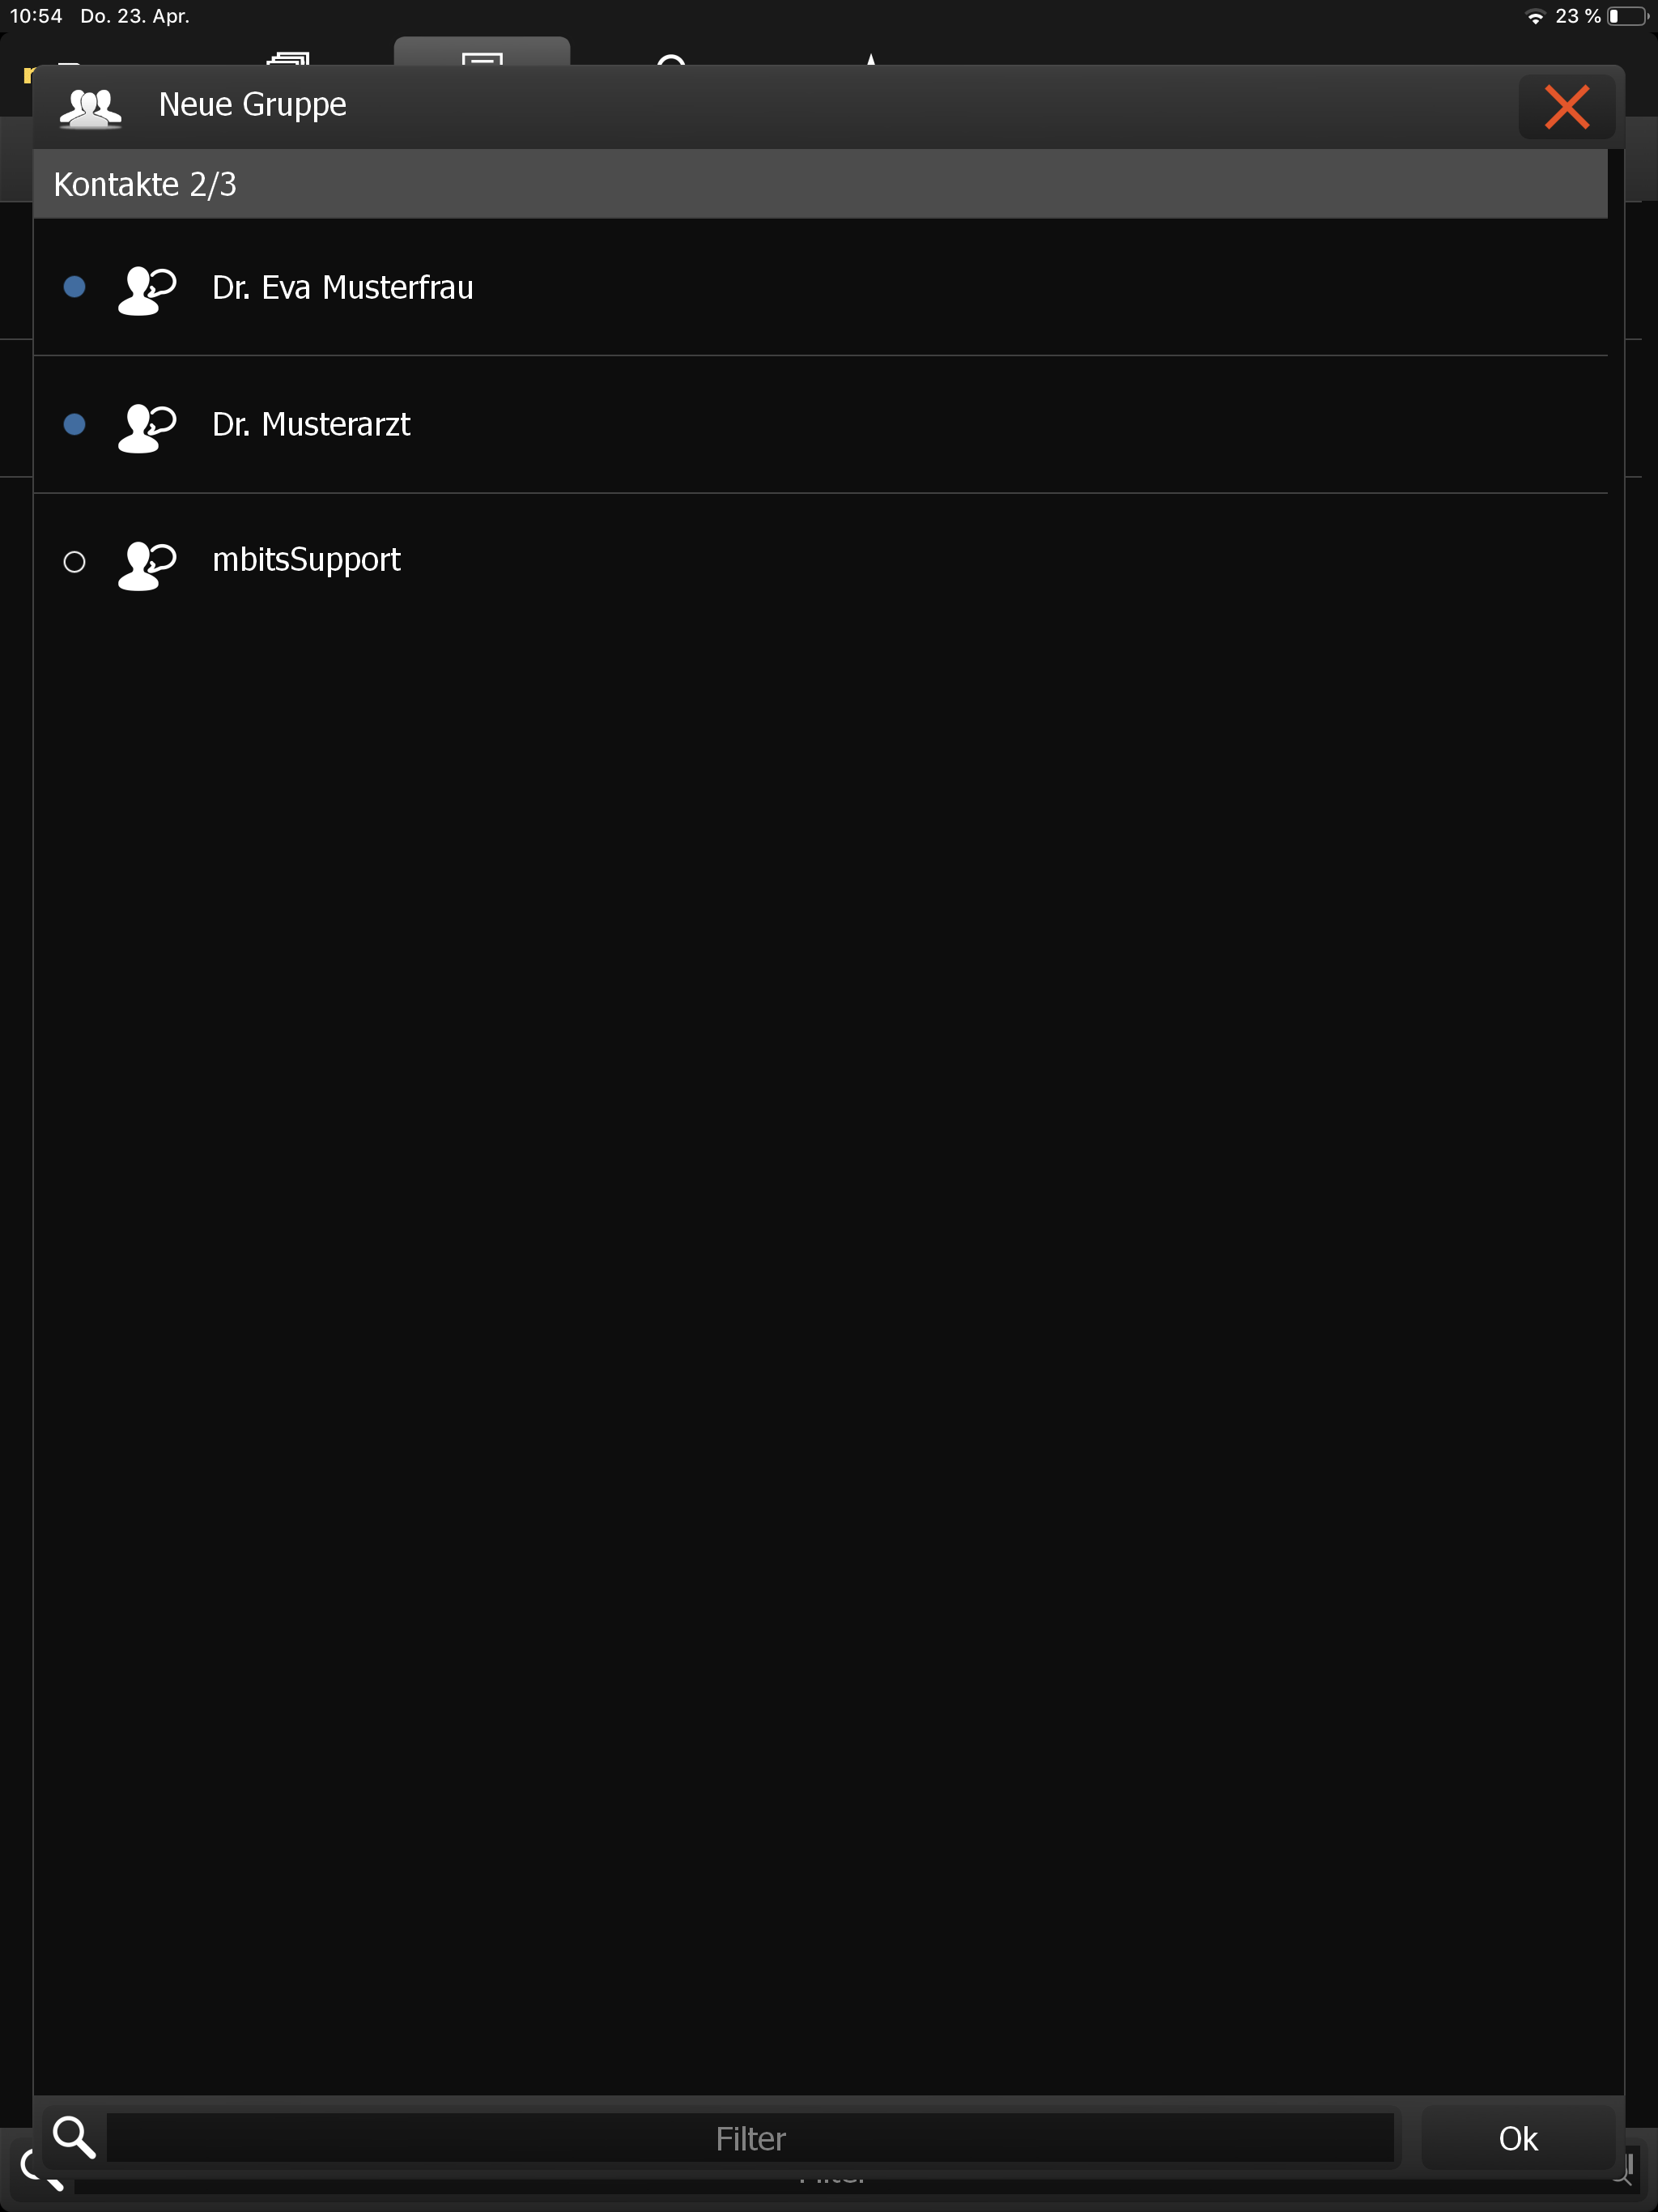

Um mit mehreren Leuten gleichzeitig zu kommunizieren, bietet es sich an, eine Chatgruppe zu erstellen (siehe Messaging). Dabei müssen die Gruppen-Mitglieder während des Erstellvorgangs selektiert werden, wie in Gruppenmitglieder auswählen zu sehen ist.